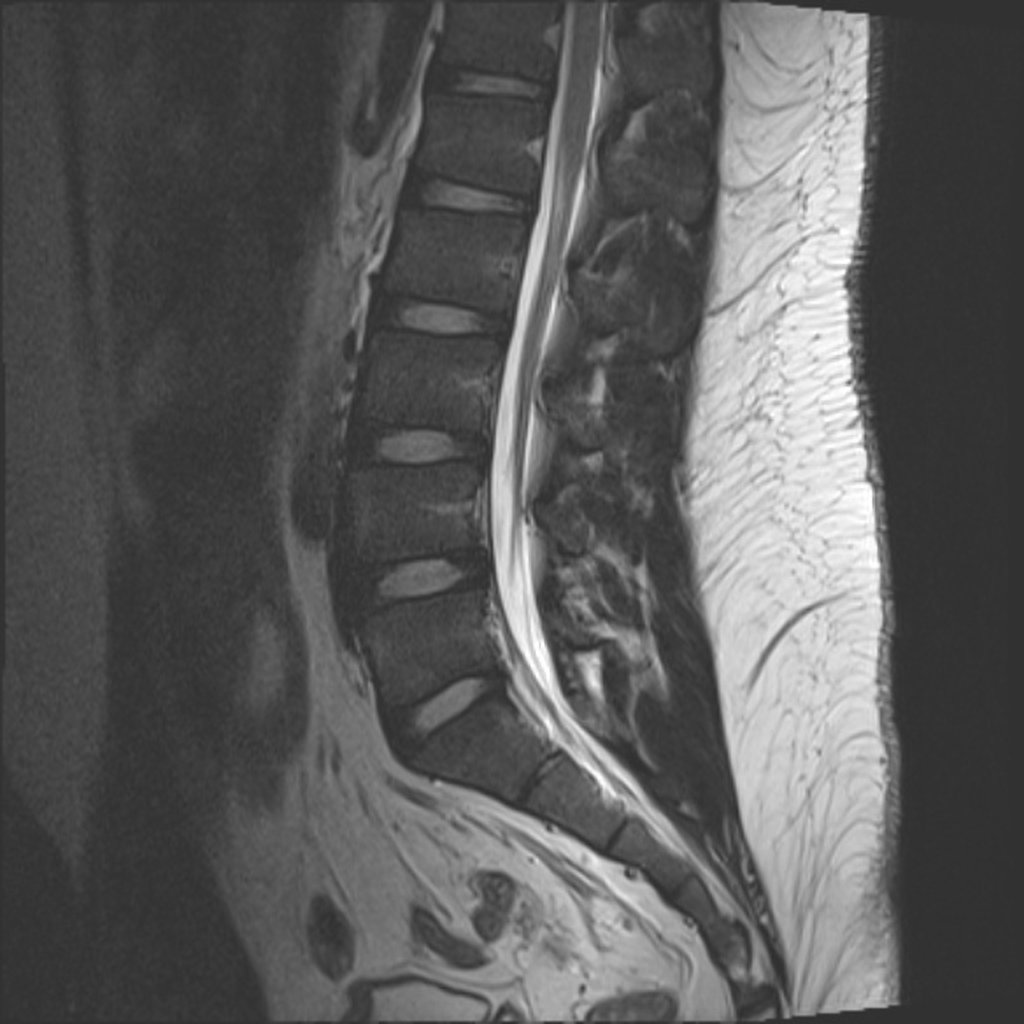

Lumbosacraal radiculair syndroom =

"Uitstralende pijn in één bil of been, al dan niet met andere prikkelingsverschijnselen en neurologische uitvalsverschijnselen, die suggestief is voor een prikkeling van één (of twee) specifieke lumbosacrale zenuwwortel(s)"2

Cauda Equina

Paardenstaart

Beeldvorming

• NHG (2015) NA 6 weken in samenspraak met patiënt2